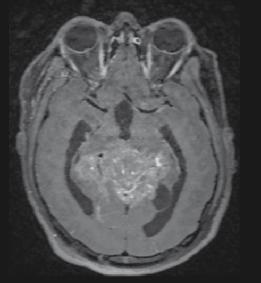

Helena Spicer

133 Favourable Response of Unresectable Giant Pinealoblastoma After Induction Chemotherapy and Craniospinal Radiotherapy: A Case Report

Laraichi R et al.

This issue includes six diverse, peerreviewed articles spanning rare case reports and forward-looking reviews. They include a rare presentation of immune checkpoint inhibitor-associated hydropneumothorax; a recurrent, aggressive, solitary plexiform neurofibroma with KRAS and AKT1 alterations; and a compelling case of unresectable giant pinealoblastoma responding favourably to induction chemotherapy followed by craniospinal radiotherapy. We also highlight a review of CAR-T cell-based immunotherapeutic strategies in hepatocellular carcinoma, a clinically significant case of aggressive angiomyxoma in term pregnancy, and a multi-omics exploration in non-small cell lung cancer aimed at advancing biomarker and pathway discovery.